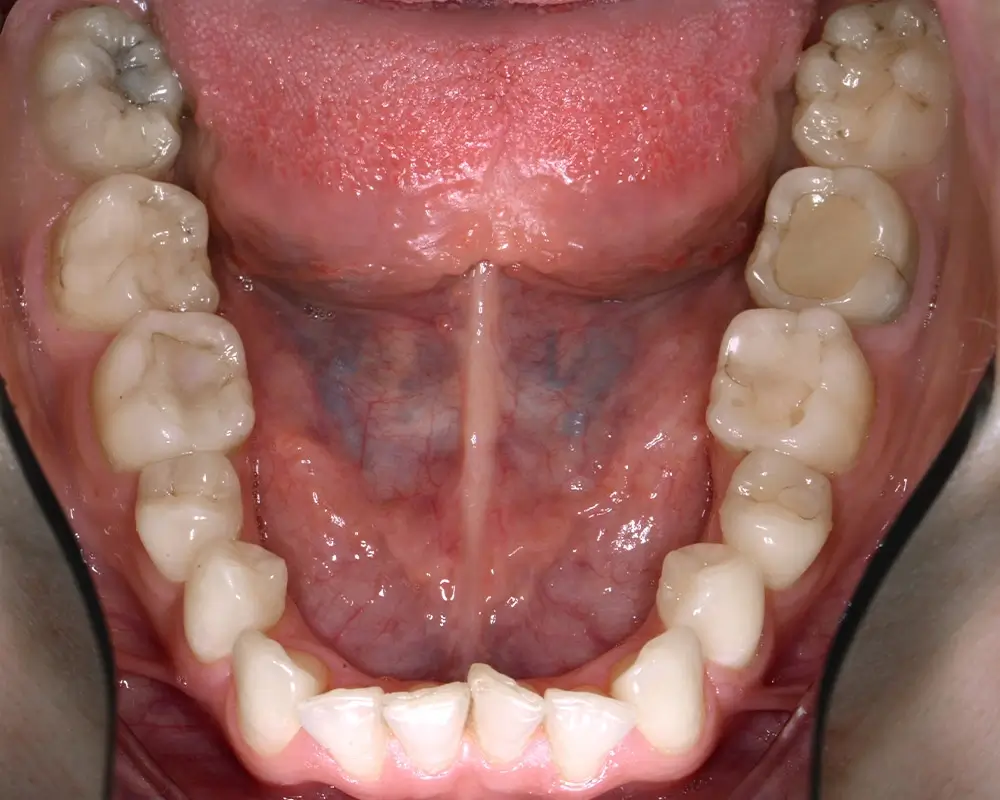

Эффективность устранения дефекта прикуса посредством элайнеров FlexiLigner.

Результаты лечения

ДО

ортодонтЭффективность устранения дефекта прикуса посредством элайнеров FlexiLigner.